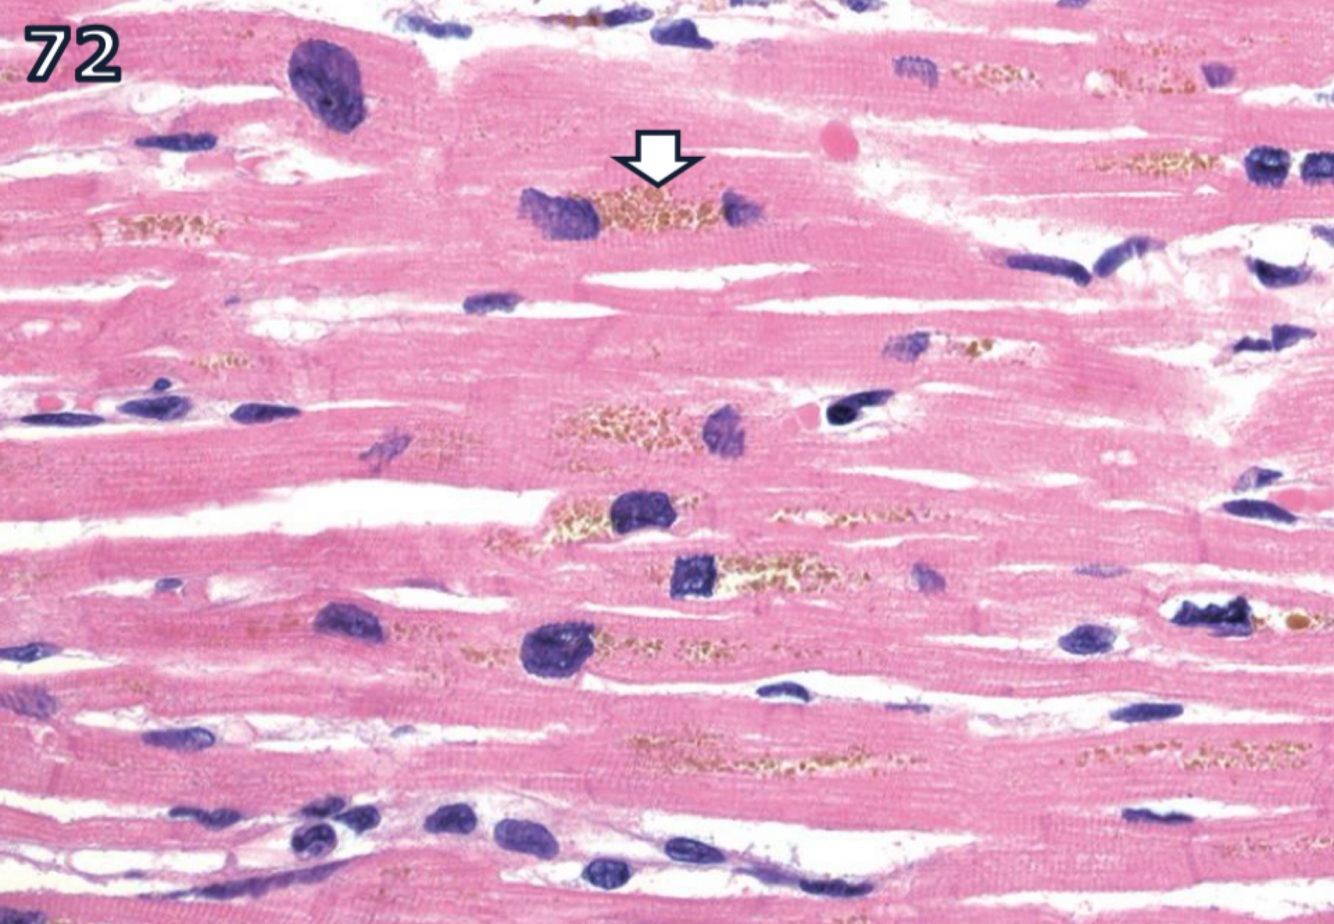

yellow-brown lipoprotein

- accumulates as residual bodiesin secondary lysosomes

- esp. in long-lived post-mitotic cells

- esp. in aged animals

known as wear-&-tear pigment of aging

- accumulation in myocardium has linear correlation with age of dog

- little or no bad effect on cells

autoflourescent

reacts w/ fat stains

carb moieties = PAS +